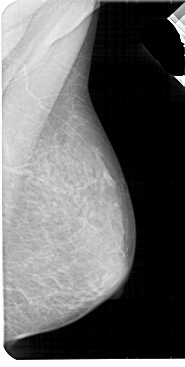

A_1947_1.LEFT_CC

LEFT_CC LINES 5356 PIXELS_PER_LINE 2806 BITS_PER_PIXEL 12 RESOLUTION 43.5 OVERLAY